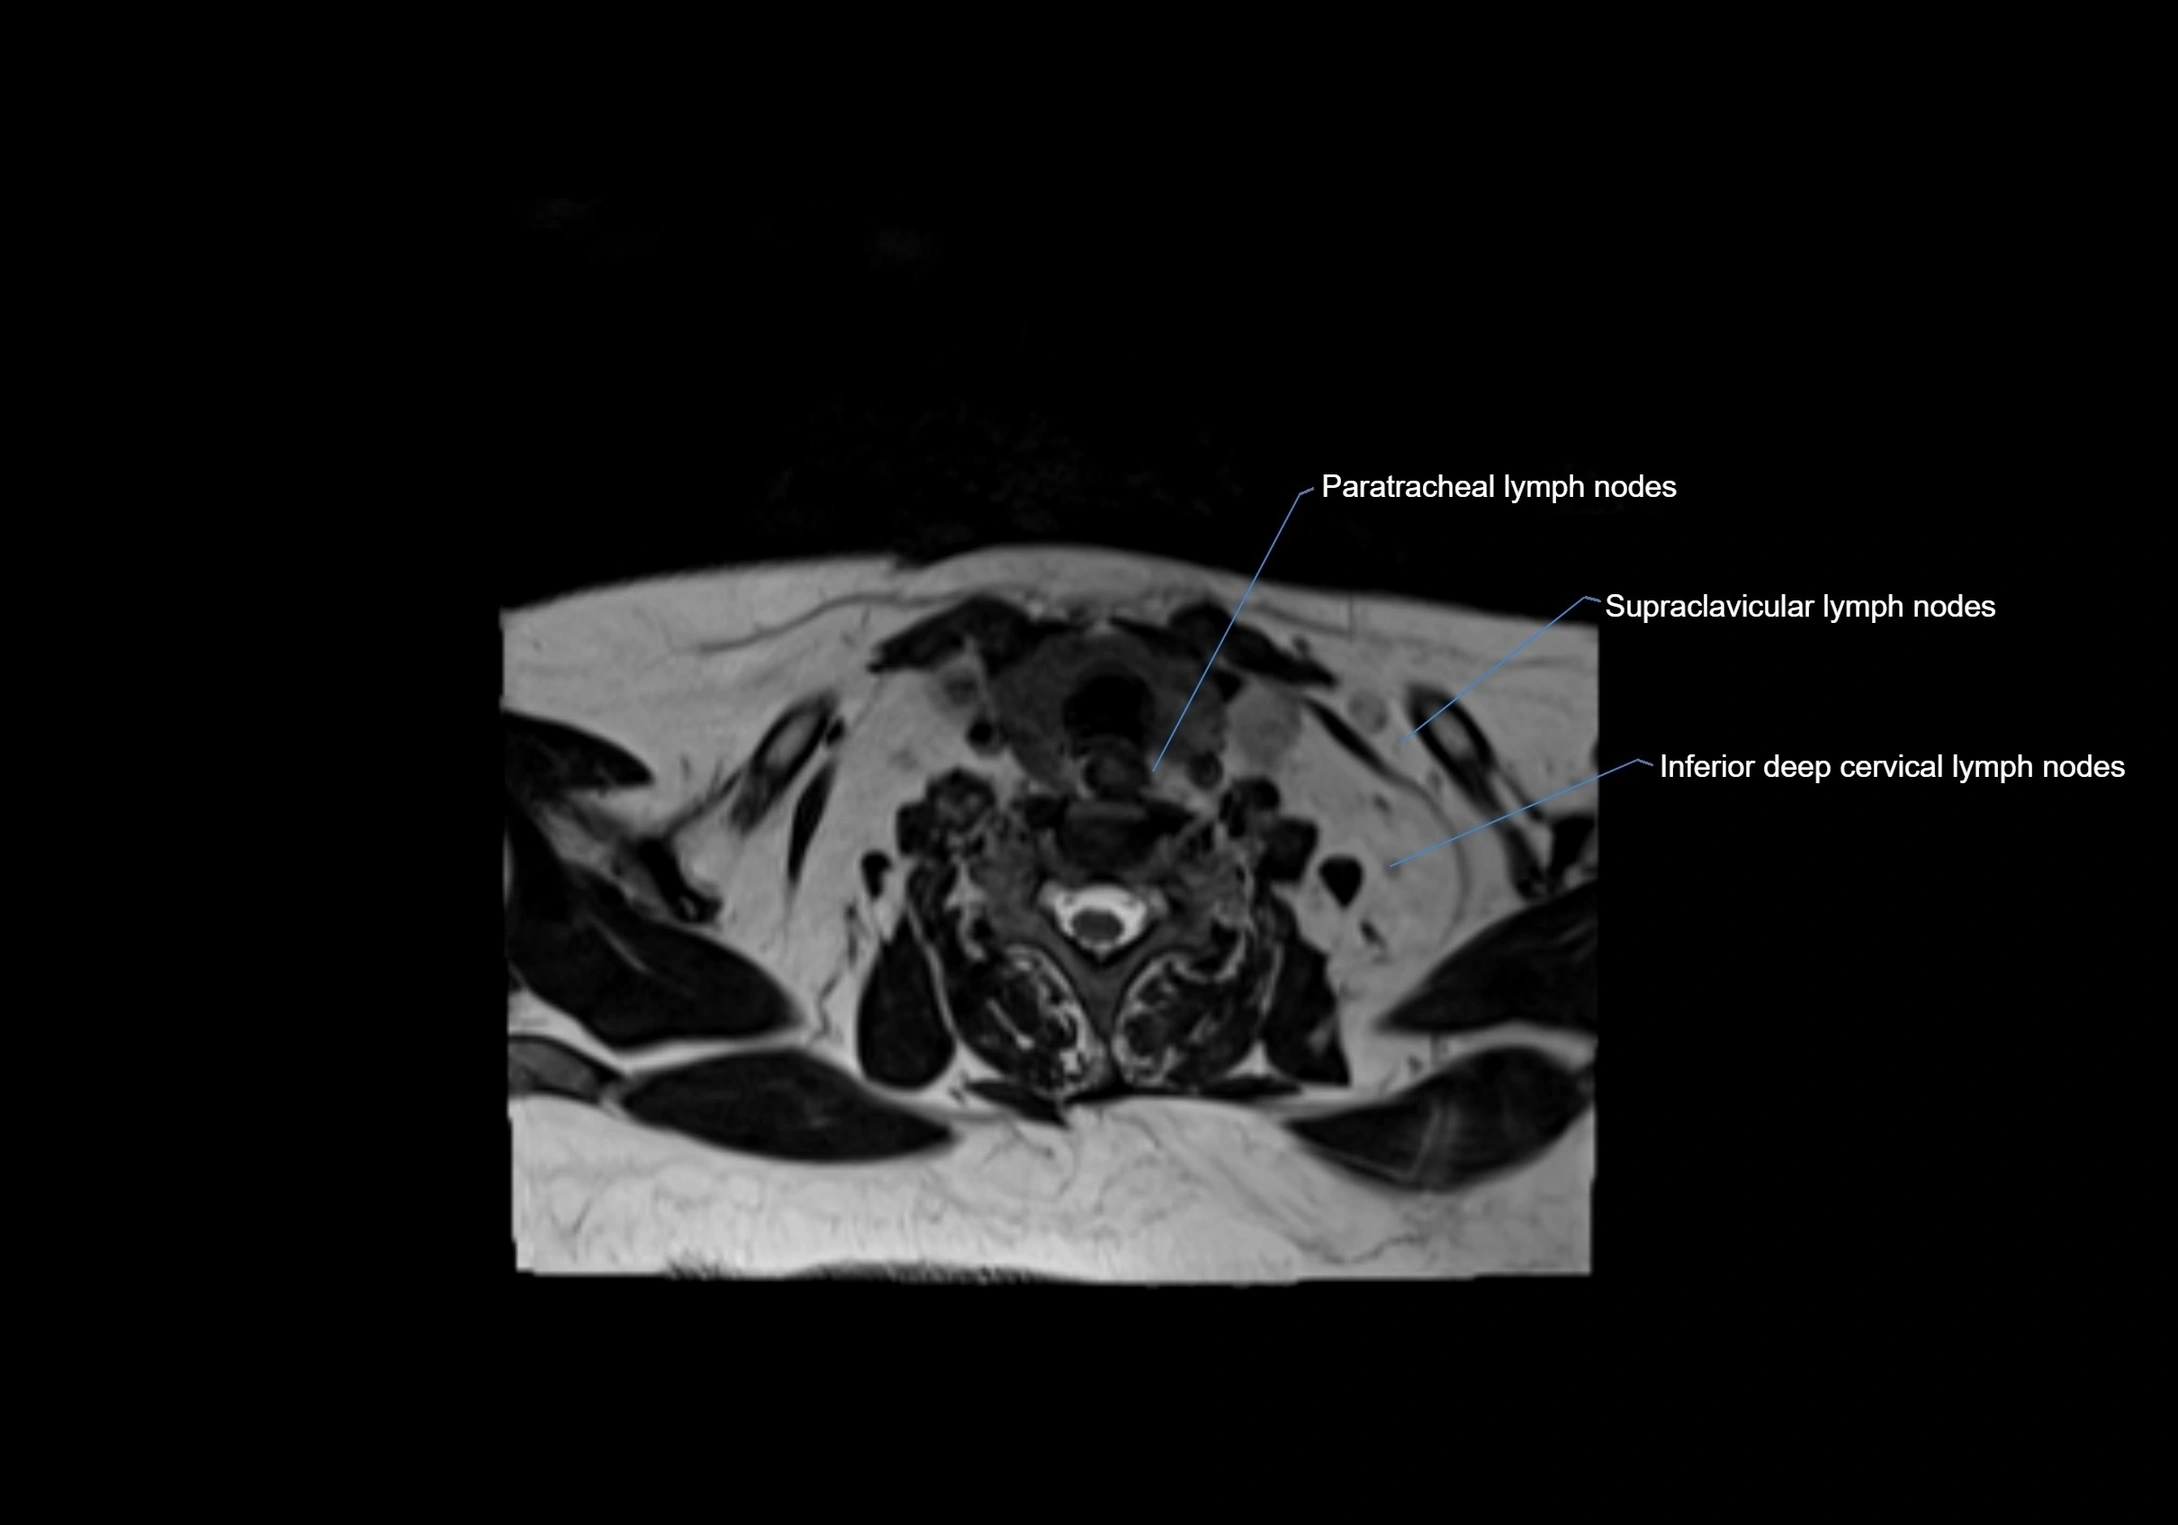

Location

• Found along primary lymph node chains, including preauricular, submandibular, parotid, and occipital regions

• Embedded in subcutaneous fat or superficial fascia, often lateral or posterior to primary nodes

• Variable in number; may occur unilaterally or bilaterally, depending on individual anatomy

MRI Appearance

T1-weighted images:

• Normal accessory nodes appear as small, oval hypointense to intermediate signal structures within subcutaneous fat

• Surrounded by hyperintense fat, enhancing contrast for visualization

CT Appearance:

• Nodes appear as small, soft tissue density structures embedded in subcutaneous fat near primary lymph nodes

• Surrounded by air in adjacent facial cavities or normal soft tissue, providing natural contrast

• Enlarged or pathological nodes appear as well-defined or irregular soft tissue masses

• CT is particularly useful for preoperative assessment, infection evaluation, or detection of metastatic spread

MRI images

image